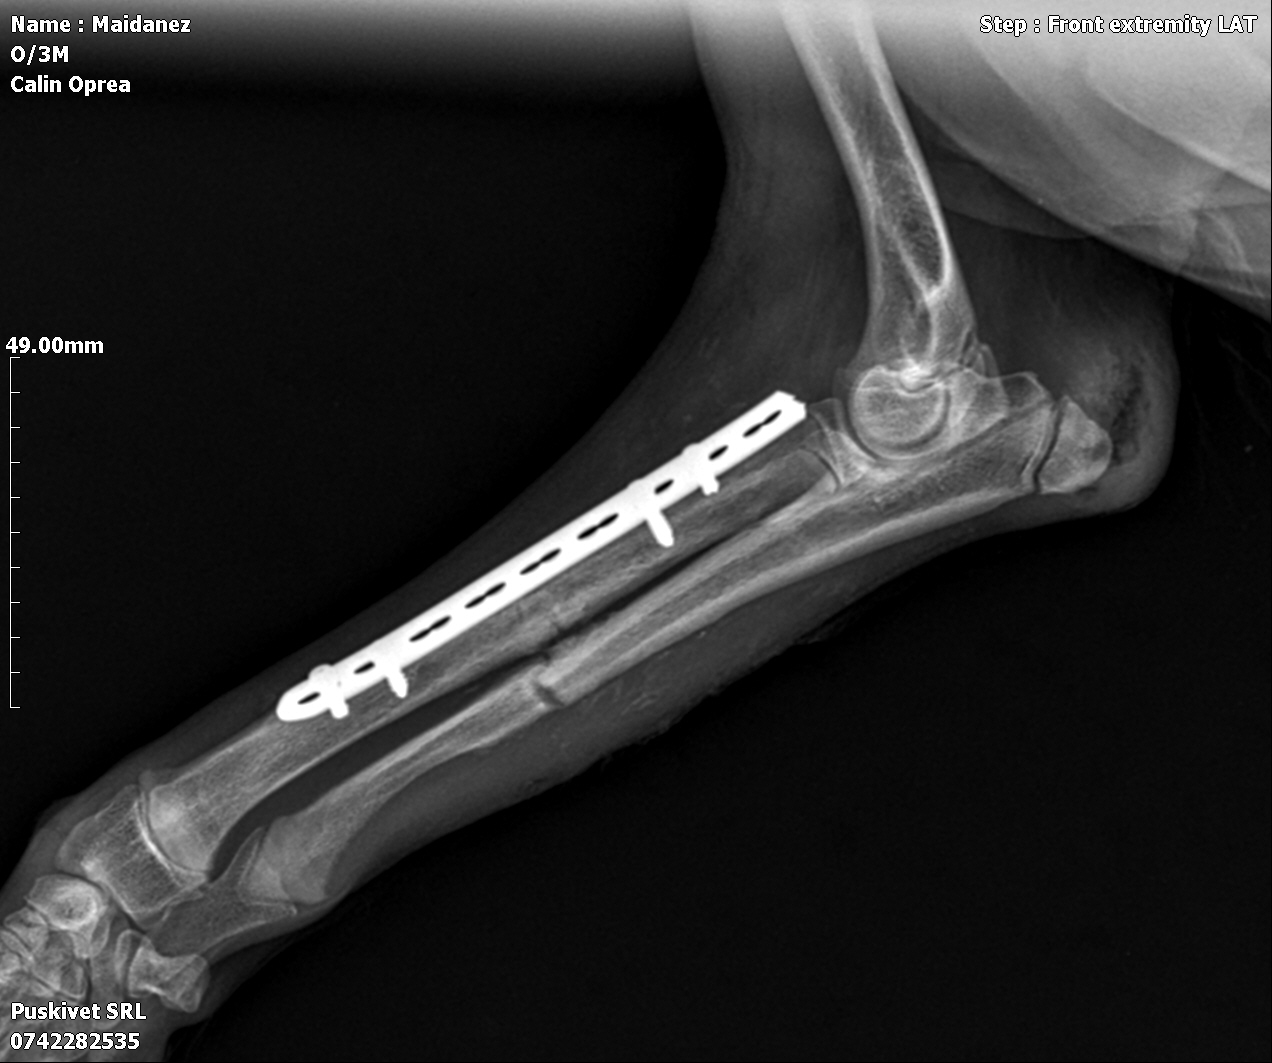

Le jour de l’An, une famille l’a trouvé seul, blessé et complètement démuni. Une radio a révélé une fracture à la patte avant droite. Il a été opéré, soigné et entouré avec beaucoup de douceur. Aujourd’hui, il a parfaitement récupéré et mène une vie tout à fait normale : il court, joue et profite de chaque instant.